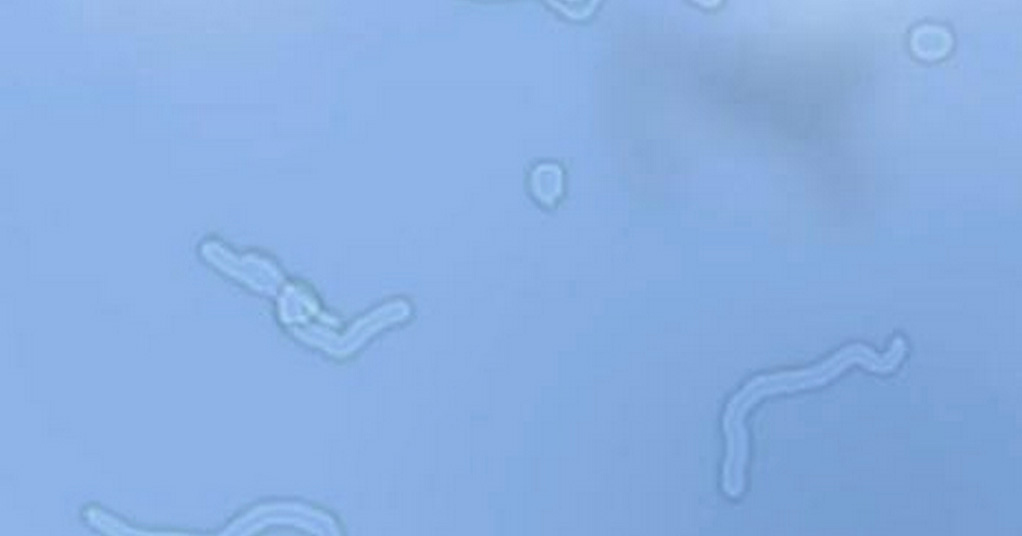

Eye Floaters Young Adults . They are often not a cause for concern and are. Many people over age 50 experience eye floaters. They appear as gray or black specks, cobwebs, or strings that float around when your eyes move. Most people have floaters that come and go, and they often. Learn more about this common problem, including causes, other risk factors and treatment options. Eye floaters are spots you might see in your field of vision. If you try to look at them directly,. For most people, eye floaters start to show up between the ages of 50 and 70. Eye floaters are dots or specks in a person’s vision that seem to float away when the person tries to look directly at them. They can look like spots, threads, squiggly lines, or even little cobwebs. However, you can see the occasional floater any time before then. Eye floaters are visual disturbances that look like spots or wavy lines. Floaters are small dark shapes that float across your vision. They come in many different shapes:

Eye floaters are dots or specks in a person’s vision that seem to float away when the person tries to look directly at them. Floaters are small dark shapes that float across your vision. They are often not a cause for concern and are. For most people, eye floaters start to show up between the ages of 50 and 70. Many people over age 50 experience eye floaters. Learn more about this common problem, including causes, other risk factors and treatment options. They appear as gray or black specks, cobwebs, or strings that float around when your eyes move. Eye floaters are spots you might see in your field of vision. However, you can see the occasional floater any time before then. They can look like spots, threads, squiggly lines, or even little cobwebs.

Eye Floaters Young Adults They appear as gray or black specks, cobwebs, or strings that float around when your eyes move. They can look like spots, threads, squiggly lines, or even little cobwebs. Most people have floaters that come and go, and they often. For most people, eye floaters start to show up between the ages of 50 and 70. However, you can see the occasional floater any time before then. Learn more about this common problem, including causes, other risk factors and treatment options. Eye floaters are dots or specks in a person’s vision that seem to float away when the person tries to look directly at them. If you try to look at them directly,. Many people over age 50 experience eye floaters. Eye floaters are spots you might see in your field of vision. They appear as gray or black specks, cobwebs, or strings that float around when your eyes move. Eye floaters are visual disturbances that look like spots or wavy lines. They are often not a cause for concern and are. They come in many different shapes: Floaters are small dark shapes that float across your vision.